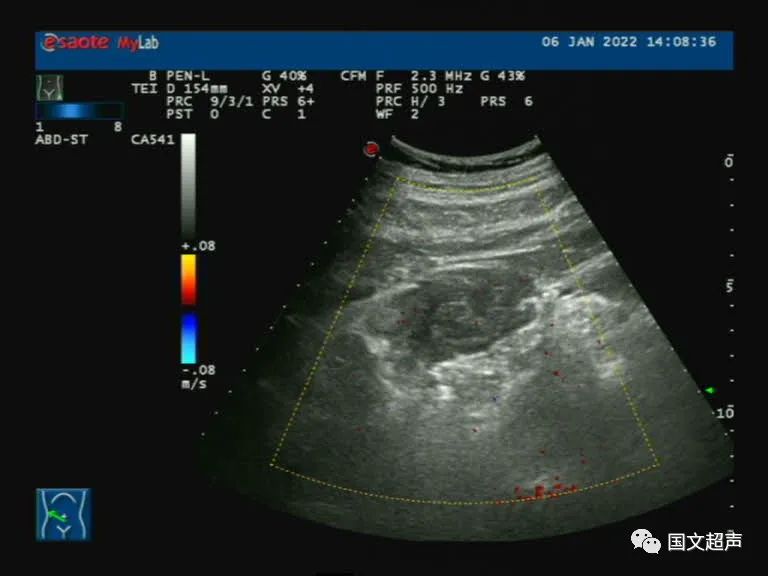

超聲檢查:右側(cè)髂肌、髂腰肌淺層及前方探及不均質(zhì)低回聲,形態(tài)不規(guī)則,邊界不清晰,CDFI:血流信號不明顯,向后方延伸至腰方肌及腰大肌之間,周圍網(wǎng)膜及脂肪組織增厚。結(jié)合增強CT檢查結(jié)果,考慮血腫,臨床觀察對癥治療。